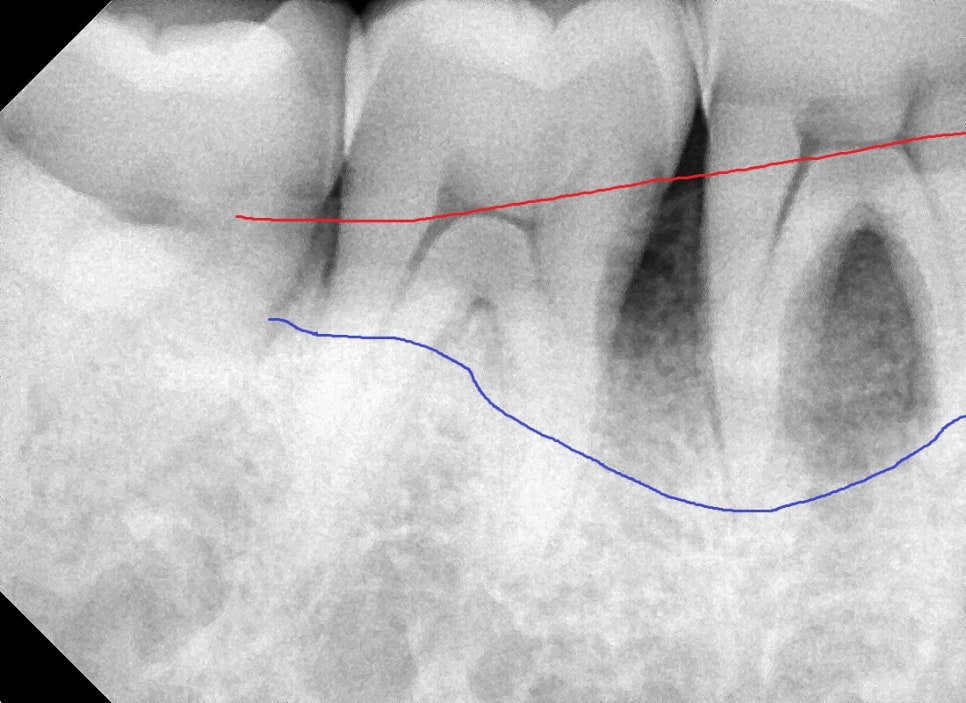

엑스레이를 찍기 전에는 잇몸에 상처가 난 것이라고 생각했는데

엑스레이를 찍어보니 특이하게도 바깥쪽이 아닌 안쪽 뼈가 파란색 선까지 파괴가 되어있었습니다.

앞서 말씀드렸듯이 치아와 잇몸 사이의 공간은 3mm 내외가 되어야 정상인데

이 경우는 10mm가 넘어가는 이미 진행이 많이 된 치주염이였습니다.